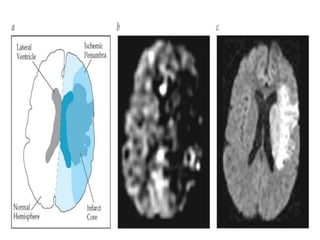

DWI images of border zone infarcts

Core of the infarct:

Ischemic penumbra:

Distribution of BrainPathology • The distribution of brain lesions caused by thrombosis is not easily distinguished from that owing to embolism. • Usually, the region of ischemia tends to lie in the center of the supply of the occluded artery. • In systemic hypoperfusion, the regions most vulnerable to ischemia are located in the border zones. • Some border zones are cortical or cortical-subcortical while others are deep. • size of the infarct depends on the – location of the occlusion, – Rate of occlusion, – adequacy of collateral circulation.

DWI images ofborder zone infarcts